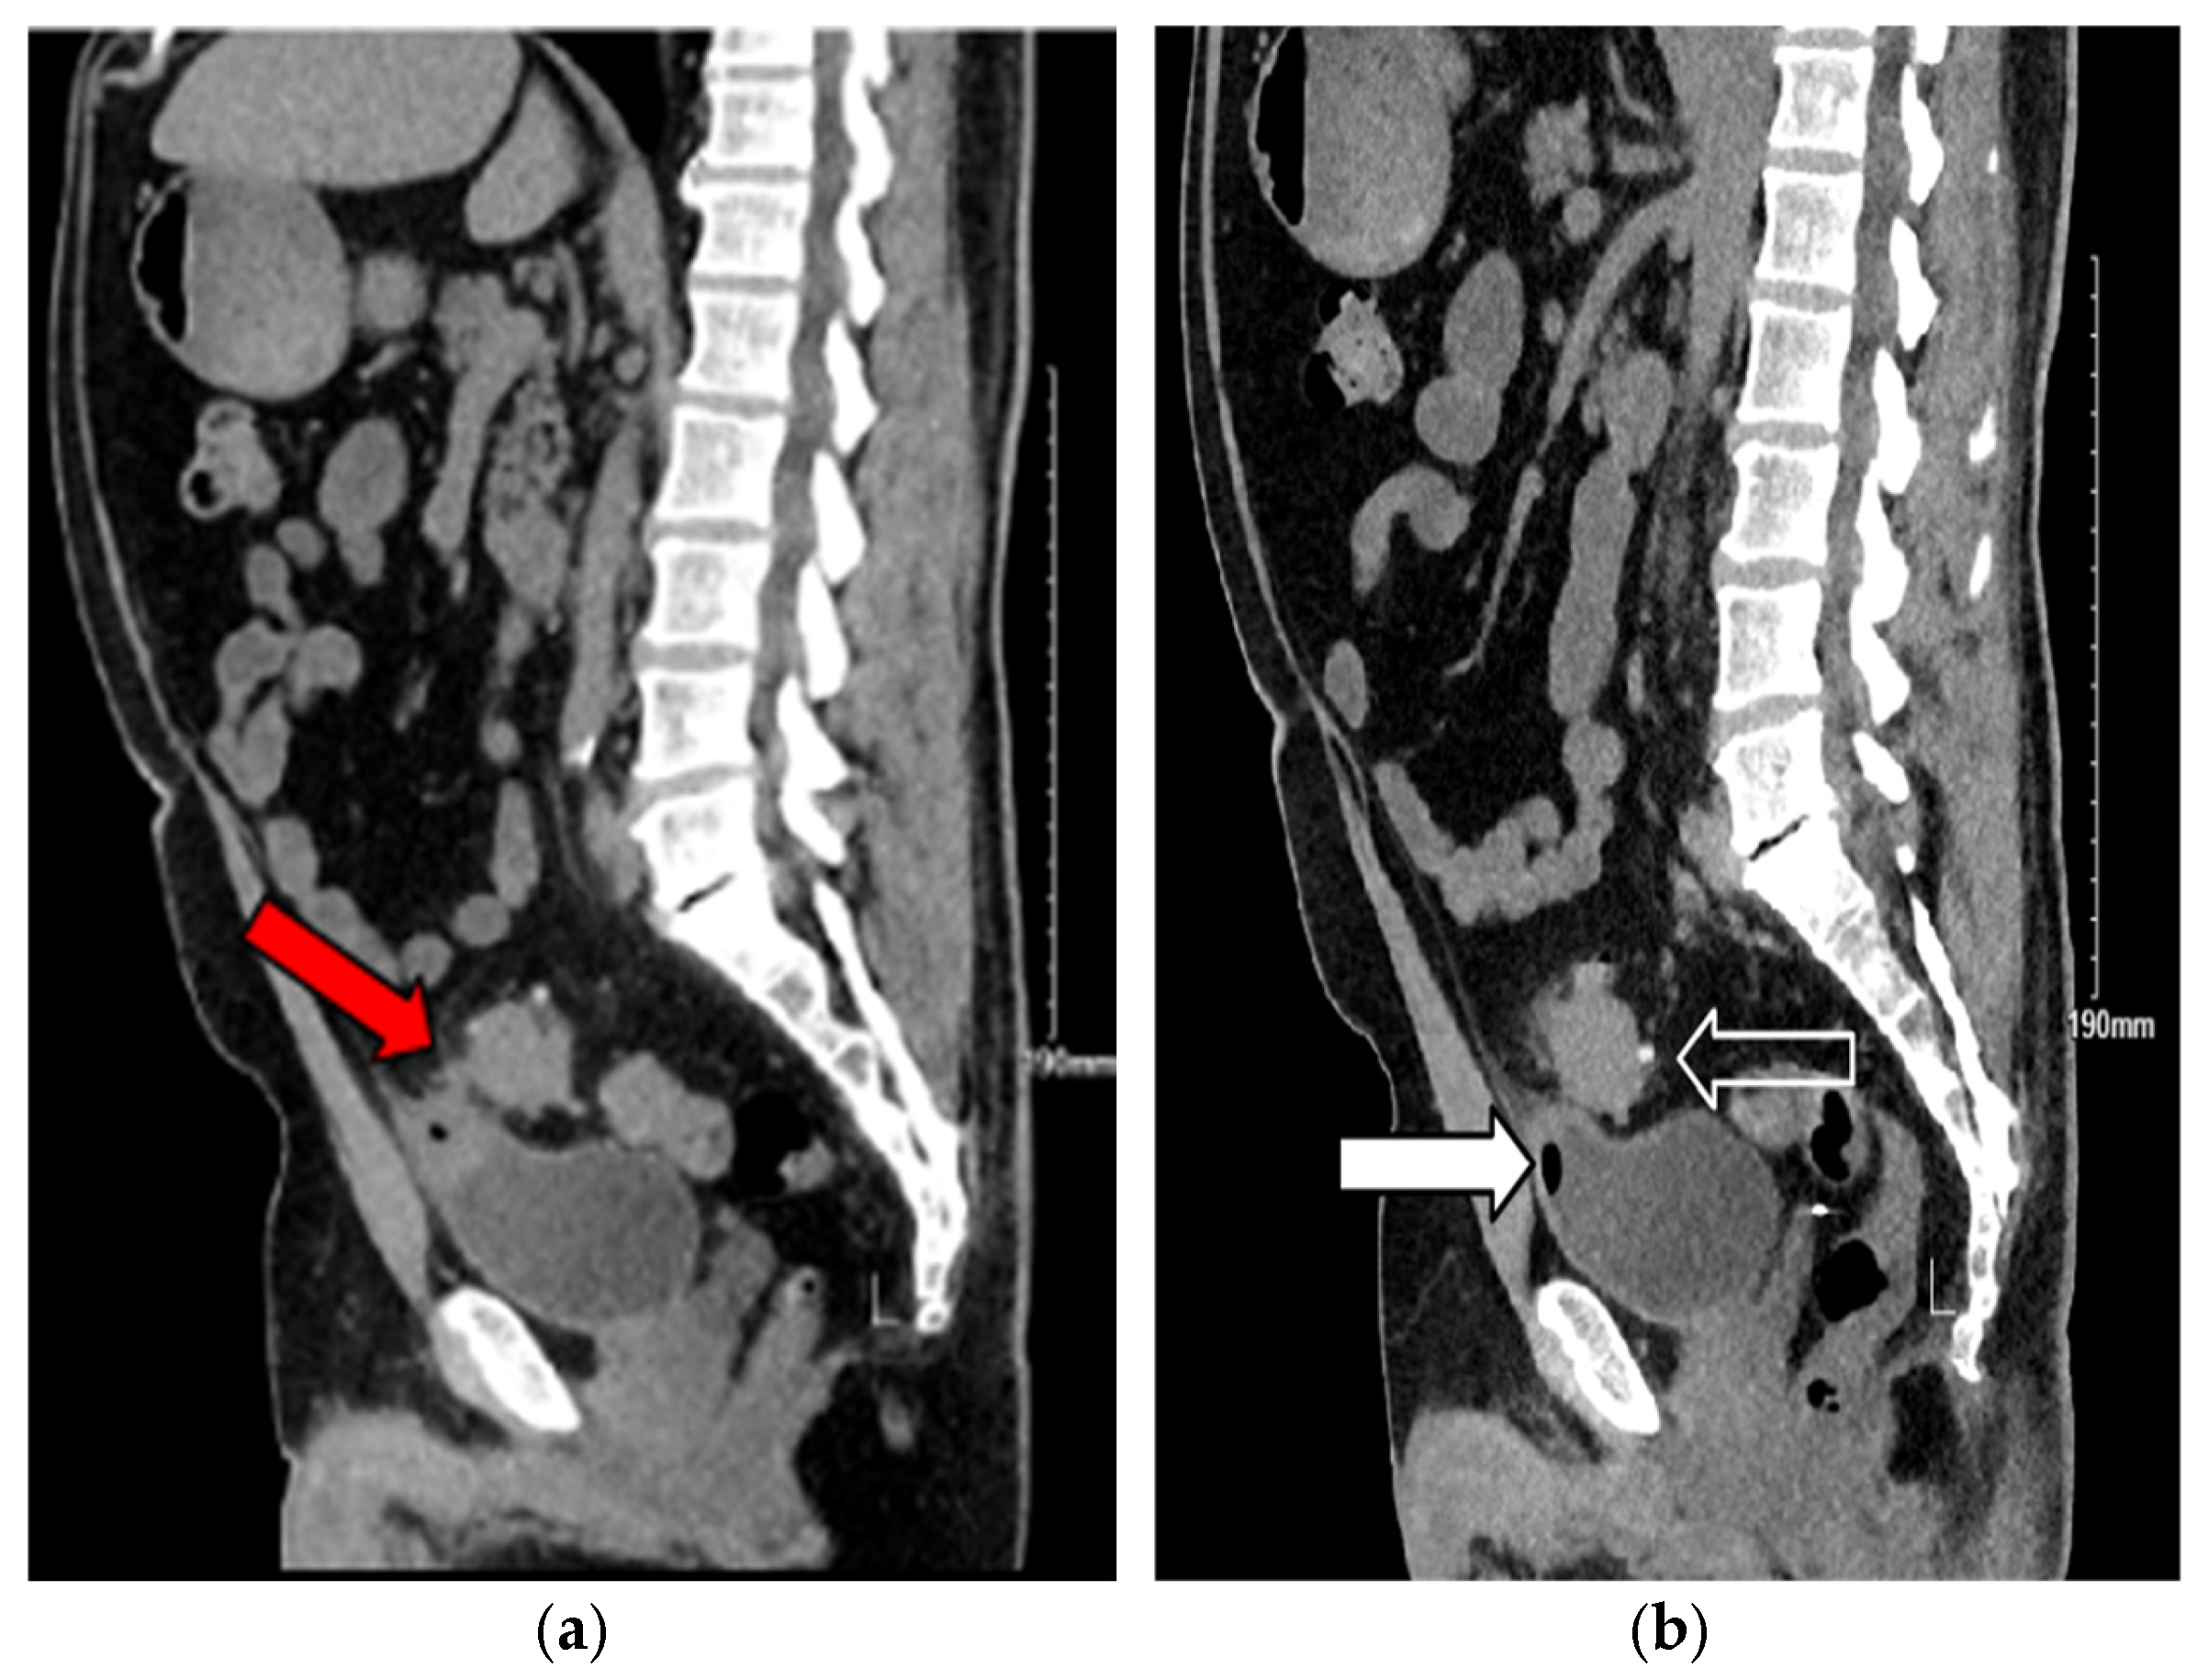

3.2. Case 2